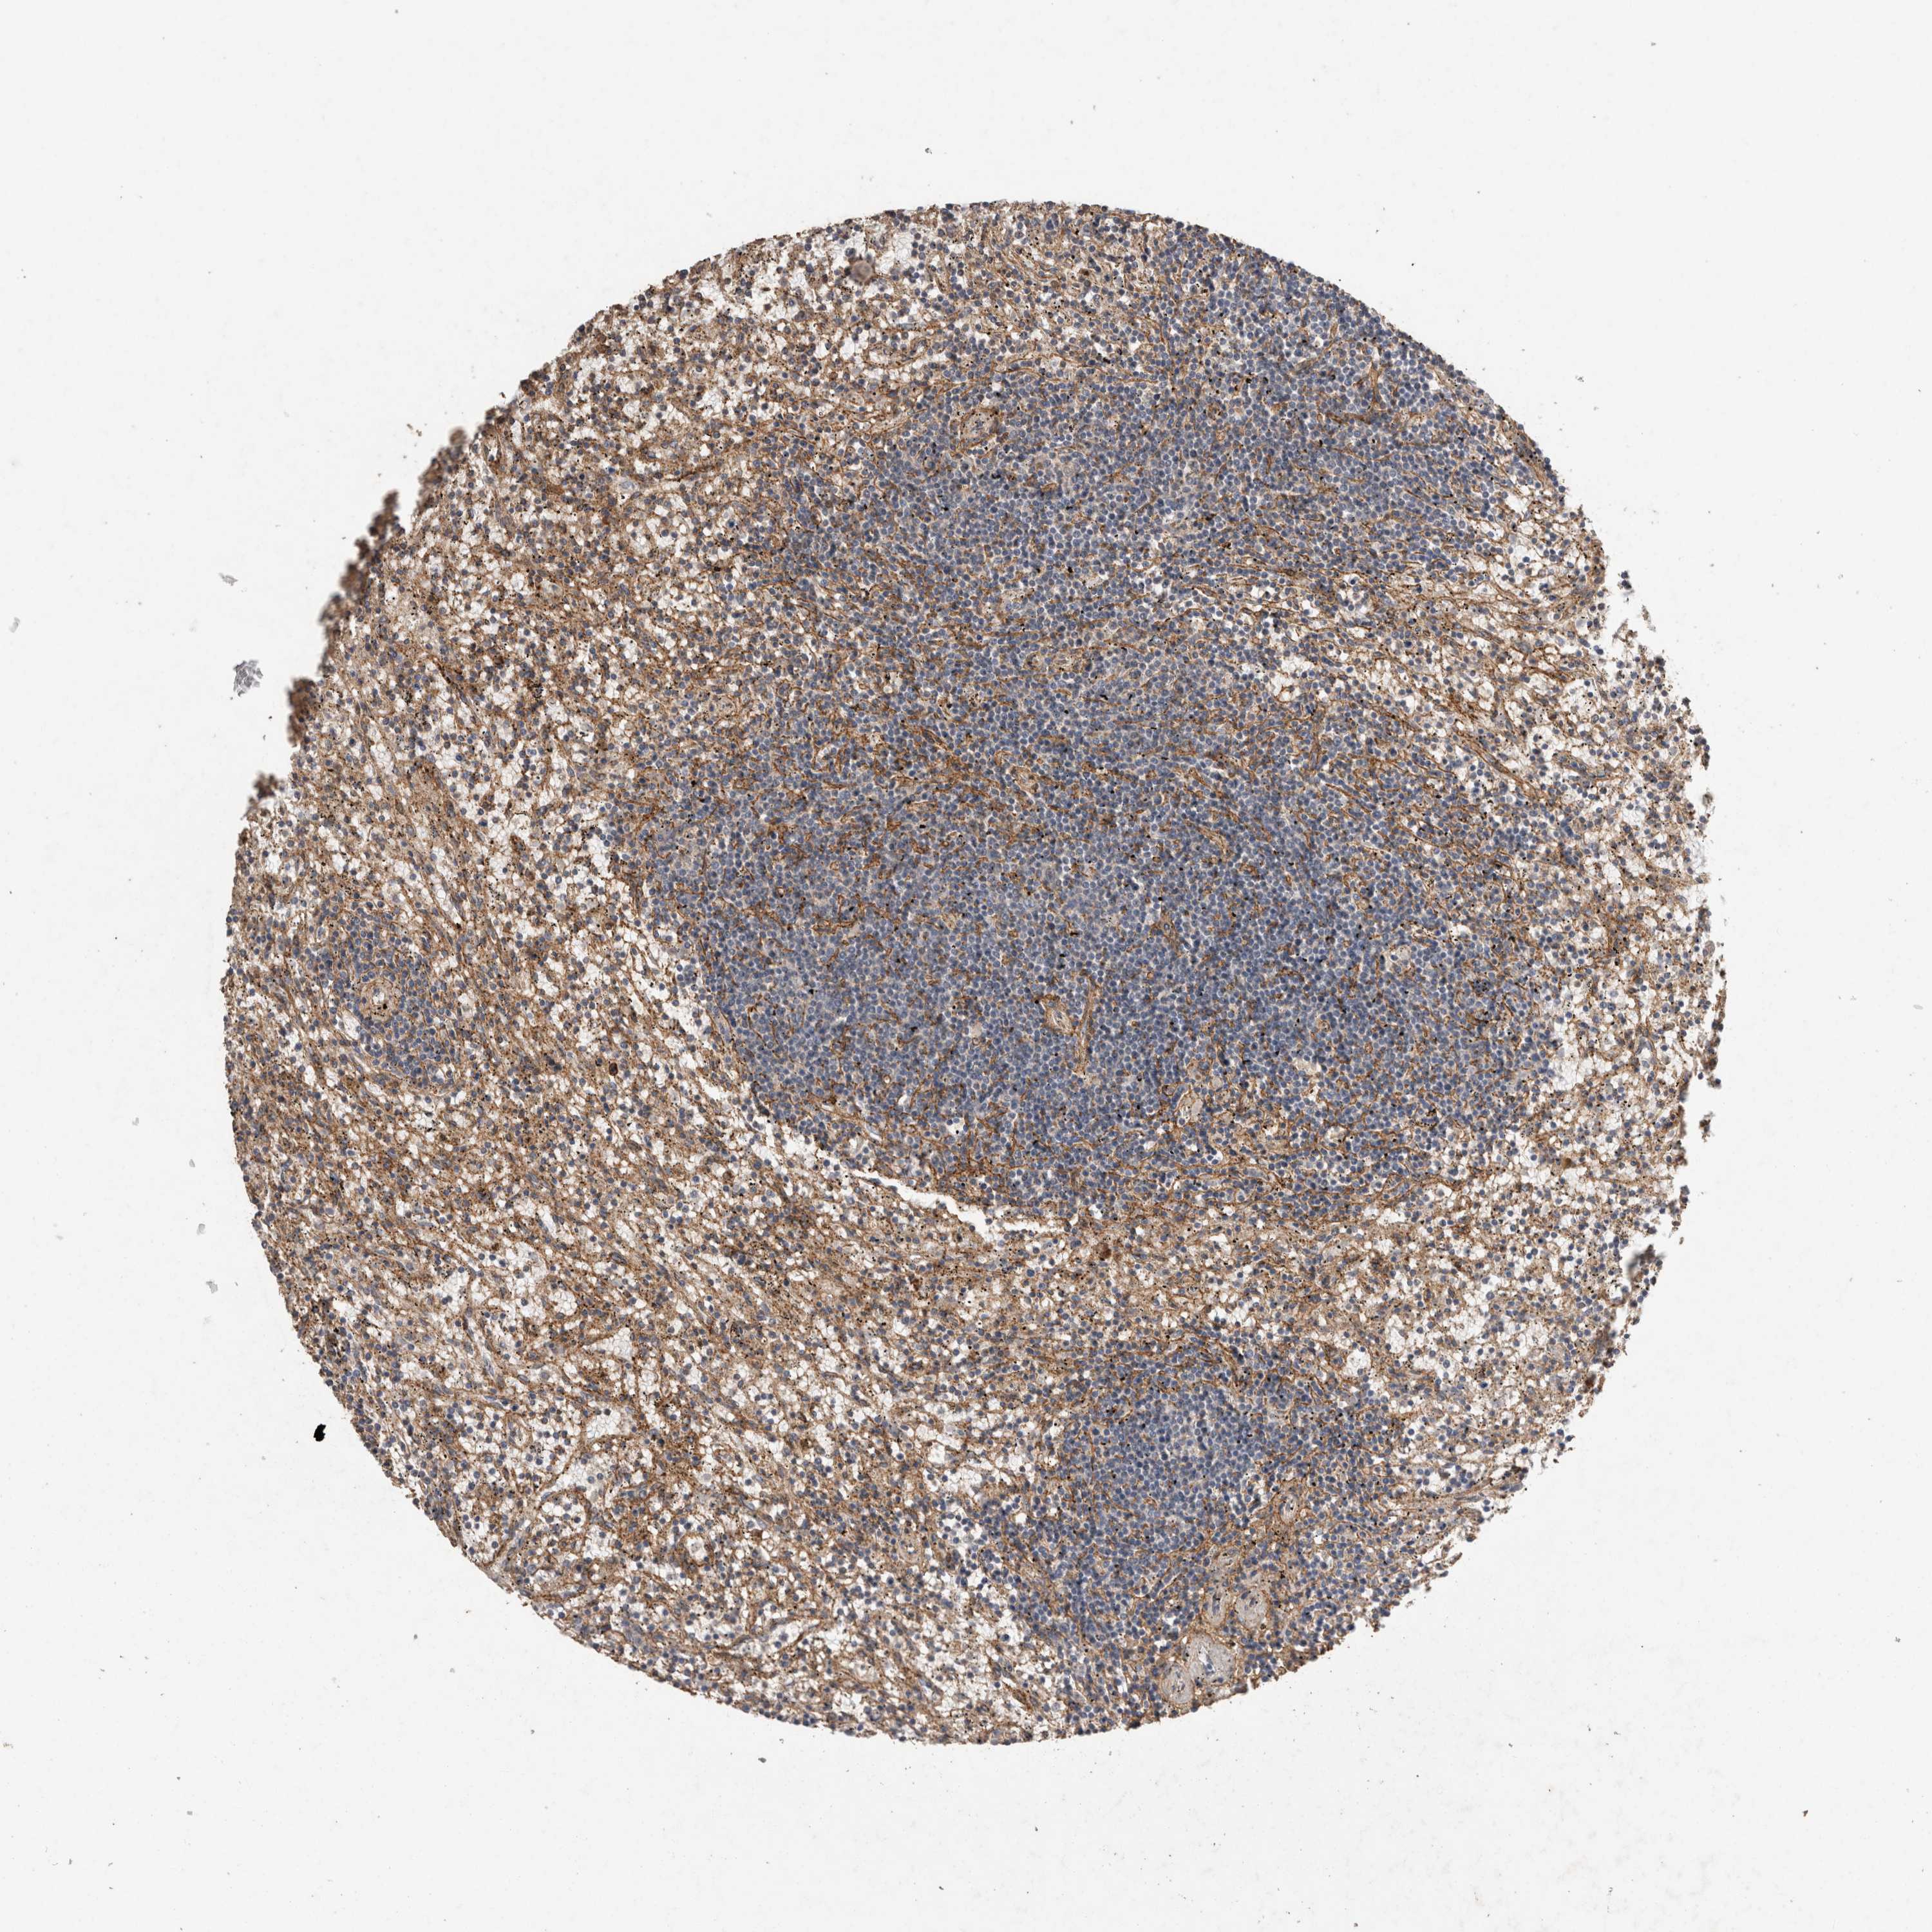

CANCER LYMPHOMA Show tissue menu

LYMPHOMA - Protein expressioni

A mouse-over function shows sample information and annotation data. Click on an image to view it in a full screen mode. Samples can be filtered based on level of antibody staining by selecting one or several of the following categories: high, medium, low and not detected. The assay and annotation is described here.

Each image is clickable and will lead to virtual microscopy that enables deeper exploration of all samples and also displays staining intensity scores, fraction scores and subcellular localization as well as patient and tissue information for each sample.

Antibody HPA038604

Antibody CAB025607

Staining

High

Medium

Low

Not detected

Intensity

Strong

Moderate

Weak

Negative

Quantity

>75%

75%-25%

<25%

None

Location

Nuclear

Cytoplasmic/membranous

Cytoplasmic/membranous,nuclear

Hodgkin's disease, NOS

Malignant lymphoma, non-Hodgkin's type, High grade

Malignant lymphoma, non-Hodgkin's type, Low grade